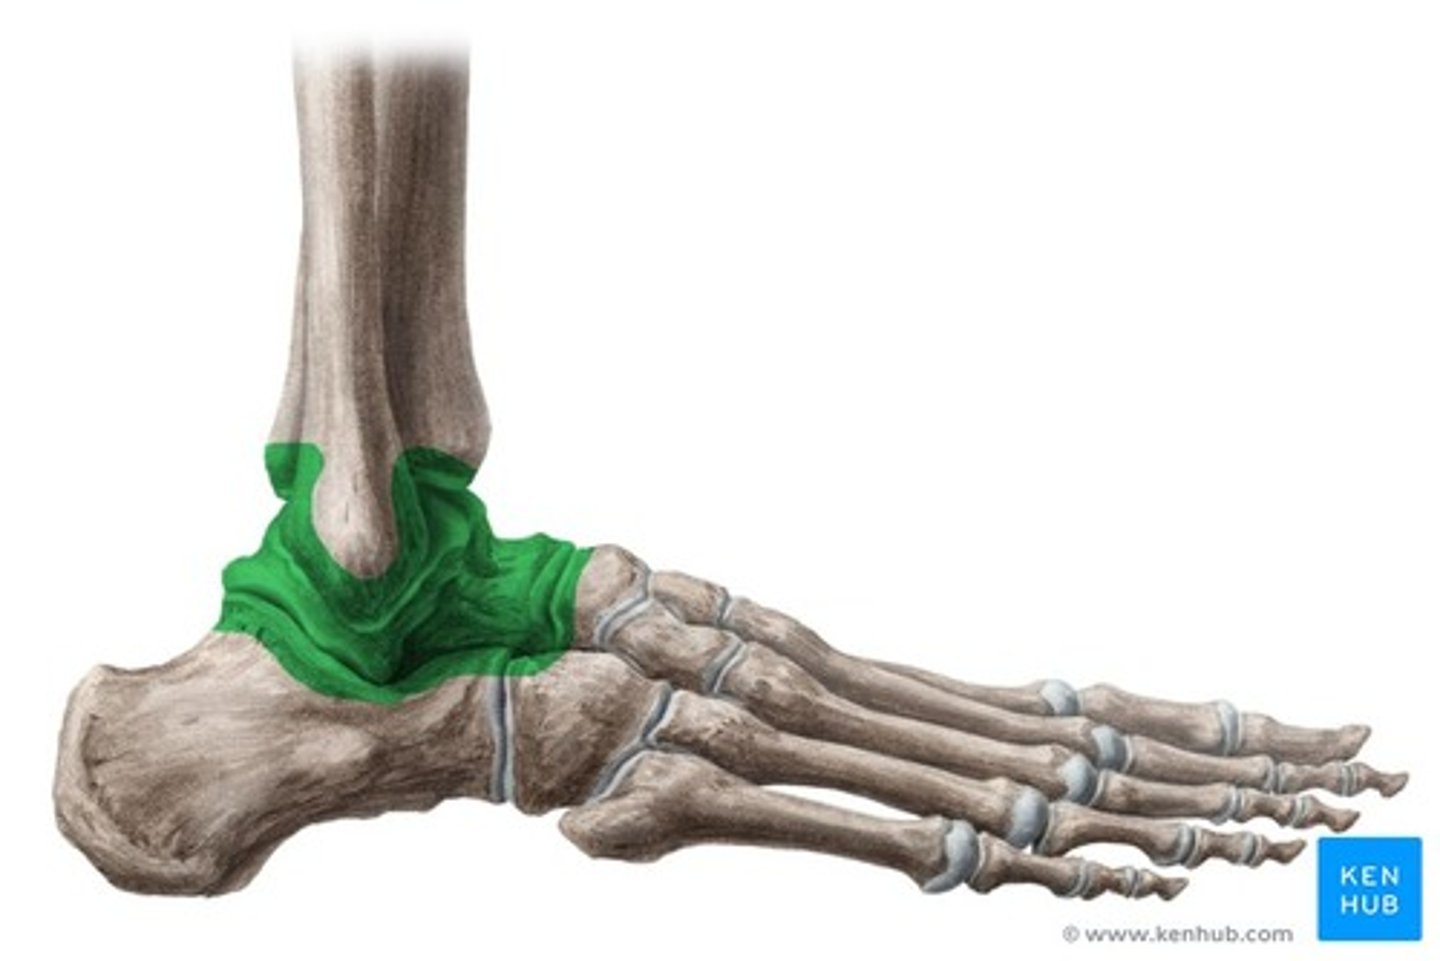

Synovial

Bones separated by joint cavity, lots of movement (knee, shoulder).

Synovial Joint Types: Ball and Socket

All directions (shoulder, hip).

Synovial Joint Types: Hinge

Back and forth (knee, elbow).

JOINT STRUCTURES: Synovial Membrane

The lining of the joint capsule that produces synovial fluid.

JOINT STRUCTURES: Synovial Fluid

Lubricates joint, reduces friction.